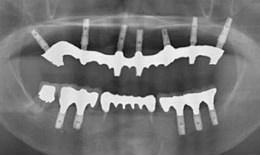

インプラント症例(4) 68歳 女性

治療方法

上顎

保存困難な歯を抜歯後、インプラントを7本埋め込み、ボーンアンカードブリッジを装着した

下顎

保存困難な歯を抜歯後、インプラントを5本埋め込み、セラミックスクラウンを被せた